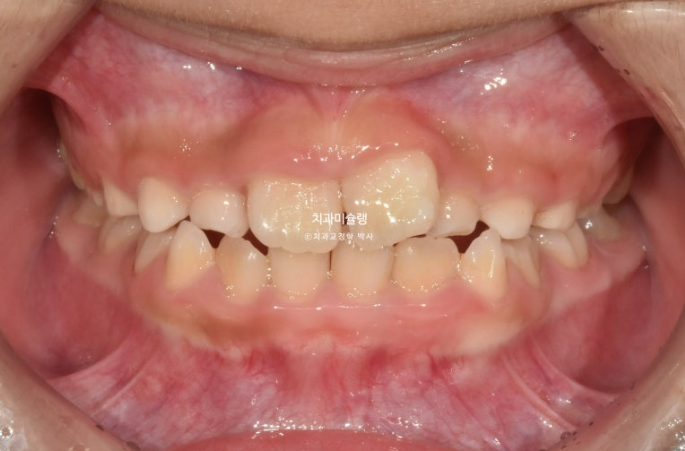

배열에서 벗어나있던 앞니가 3개월 전에 비해 좀 더 가지런하게 배열이 되어있습니다.

전 후 비교 보겠습니다.

25.04~25.09